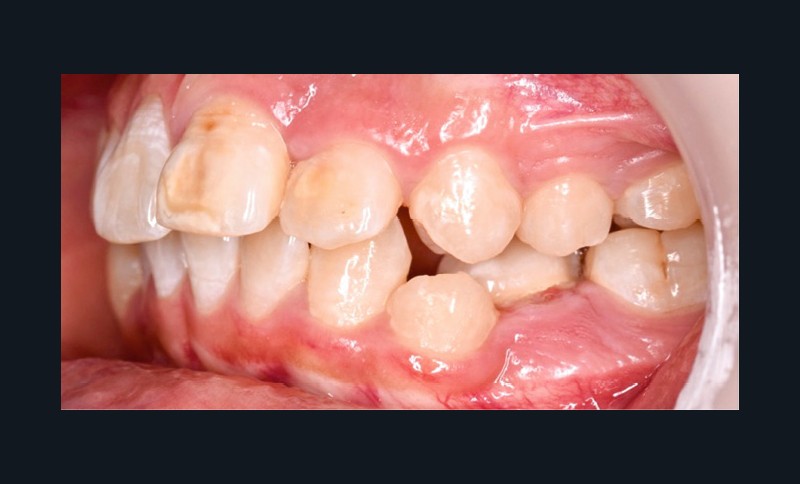

Une patiente âgée de 12 ans se présente en consultation, motivée par la position de son incisive centrale maxillaire, décrite comme « en avant », marquée par une dyschromie et une mobilité de grade 2 selon Muhlemann. L’examen clinique montre l’absence de 23 sur l’arcade, une dysharmonie dents-arcade marquée, un surplomb accentué, et une déviation des milieux inter-incisifs, conséquence du comblement spontané de l’espace de 23. L’ensemble s’inscrit dans un contexte de Classe I d’Angle molaire. L’orthopantomogramme révèle l’inclusion de 23, associée à une résorption radiculaire étendue aux deux tiers de 21. La 22 ne présente aucune altération visible.

La patiente, de profil normodivergent, présente une Classe I squelettique sans troubles fonctionnels (fig. 1-8).